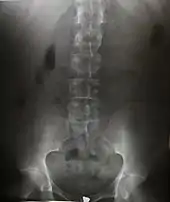

Projectional radiography

The creation of images by exposing an object to X-rays or other high-energy forms of electromagnetic radiation and capturing the resulting remnant beam (or "shadow") as a latent image is known as "projection radiography." The "shadow" may be converted to light using a fluorescent screen, which is then captured on photographic film, it may be captured by a phosphor screen to be "read" later by a laser (CR), or it may directly activate a matrix of solid-state detectors (DR—similar to a very large version of a CCD in a digital camera). Bone and some organs (such as lungs) especially lend themselves to projection radiography. It is a relatively low-cost investigation with a high diagnostic yield. The difference between soft and hard body parts stems mostly from the fact that carbon has a very low X-ray cross section compared to calcium.